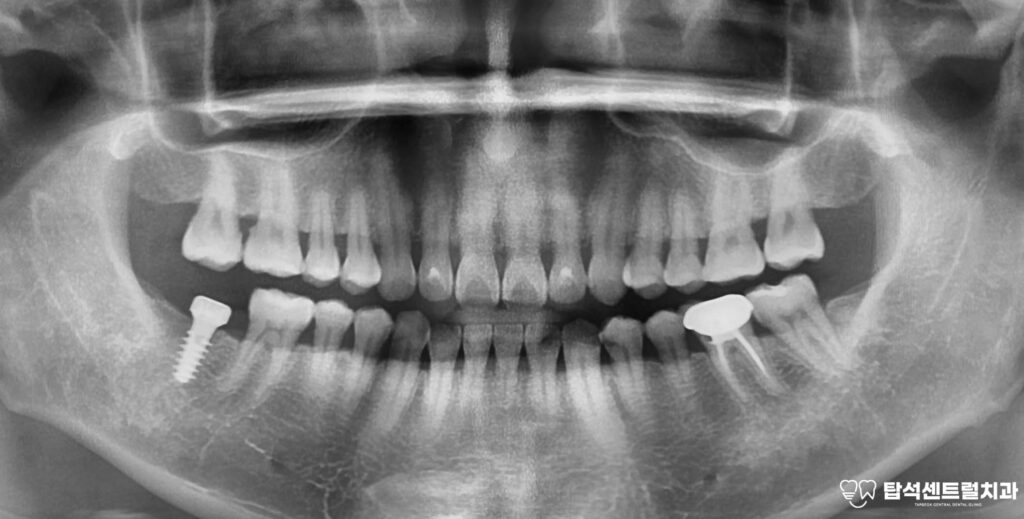

치료 경과를 확인하기 위해

일정 기간이 지난 후 CT를 재촬영하여

내부가 깨끗해졌는지 확인합니다.

영상에서 염증이 소실된 것이 확인되고

통증 역시 완전히 사라진 것을 알 수 있었습니다.

수술 후 일정 기간 동안

임플란트가 뼈와 단단히 결합하는

골유착 과정을 거치게 됩니다.

이 과정이 성공적으로 완료되면

보철물을 연결하여 마무리합니다.